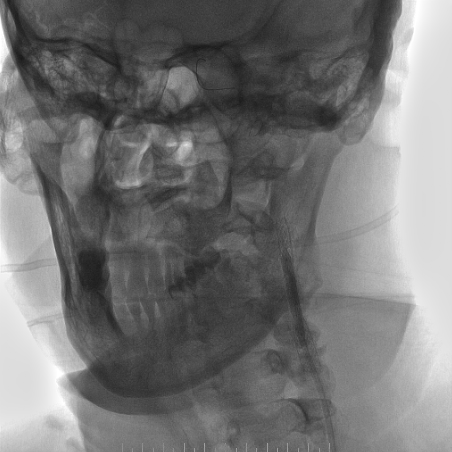

心脑联合造影

-- 右侧颈内起始部中度狭窄,经前交通向左侧代偿

-- 右侧桡动脉穿刺置入7F 泰尔茂薄壁鞘,波科7F0.081导引导管同轴5F 125cm SimmonsII导管在0.035导丝引导下引至左侧颈总动脉。

波科支架怎么样​径技·第165期|7F经桡入路下的颈动脉狭窄支架成形术一例_https://www.jmylbn.com_新闻资讯_第24张

波科支架怎么样​径技·第165期|7F经桡入路下的颈动脉狭窄支架成形术一例_https://www.jmylbn.com_新闻资讯_第25张

波科支架怎么样​径技·第165期|7F经桡入路下的颈动脉狭窄支架成形术一例_https://www.jmylbn.com_新闻资讯_第26张

-- 路途引导下,FilterWire EZ保护伞顺利通过狭窄段至左侧颈内动脉岩骨水平段,顺利释放保护伞